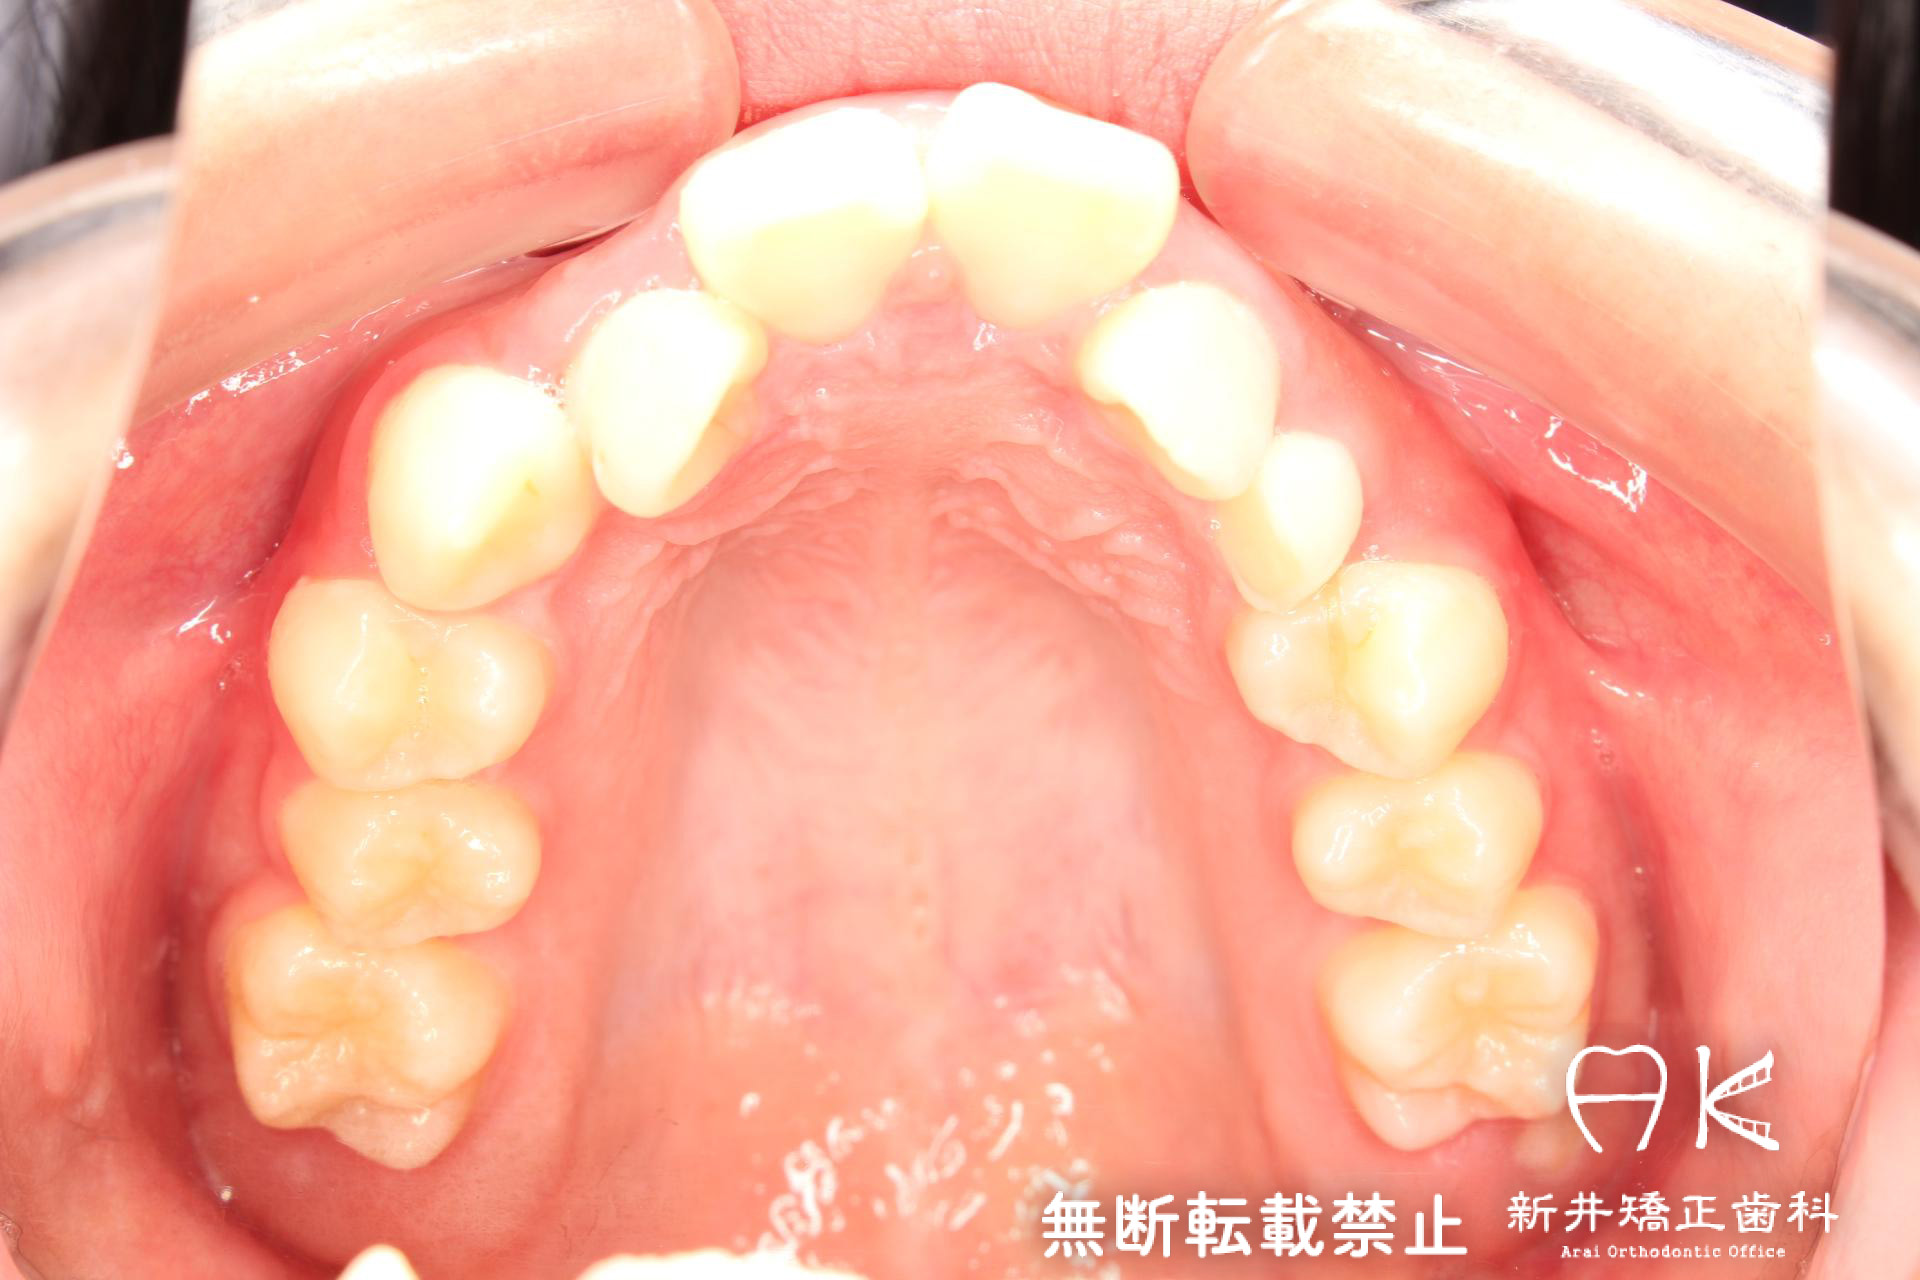

| 治療前 | 骨格的には受け口の患者さんですが、上顎前歯の唇側傾斜が大きく、患者さんとしては出っ歯だと思われていたパターンです。 元々口元の突出感はほとんどなかったため、歯を抜かずに上下顎ともに歯列を後方に移動させることにより主訴を改善させることとしました。 |